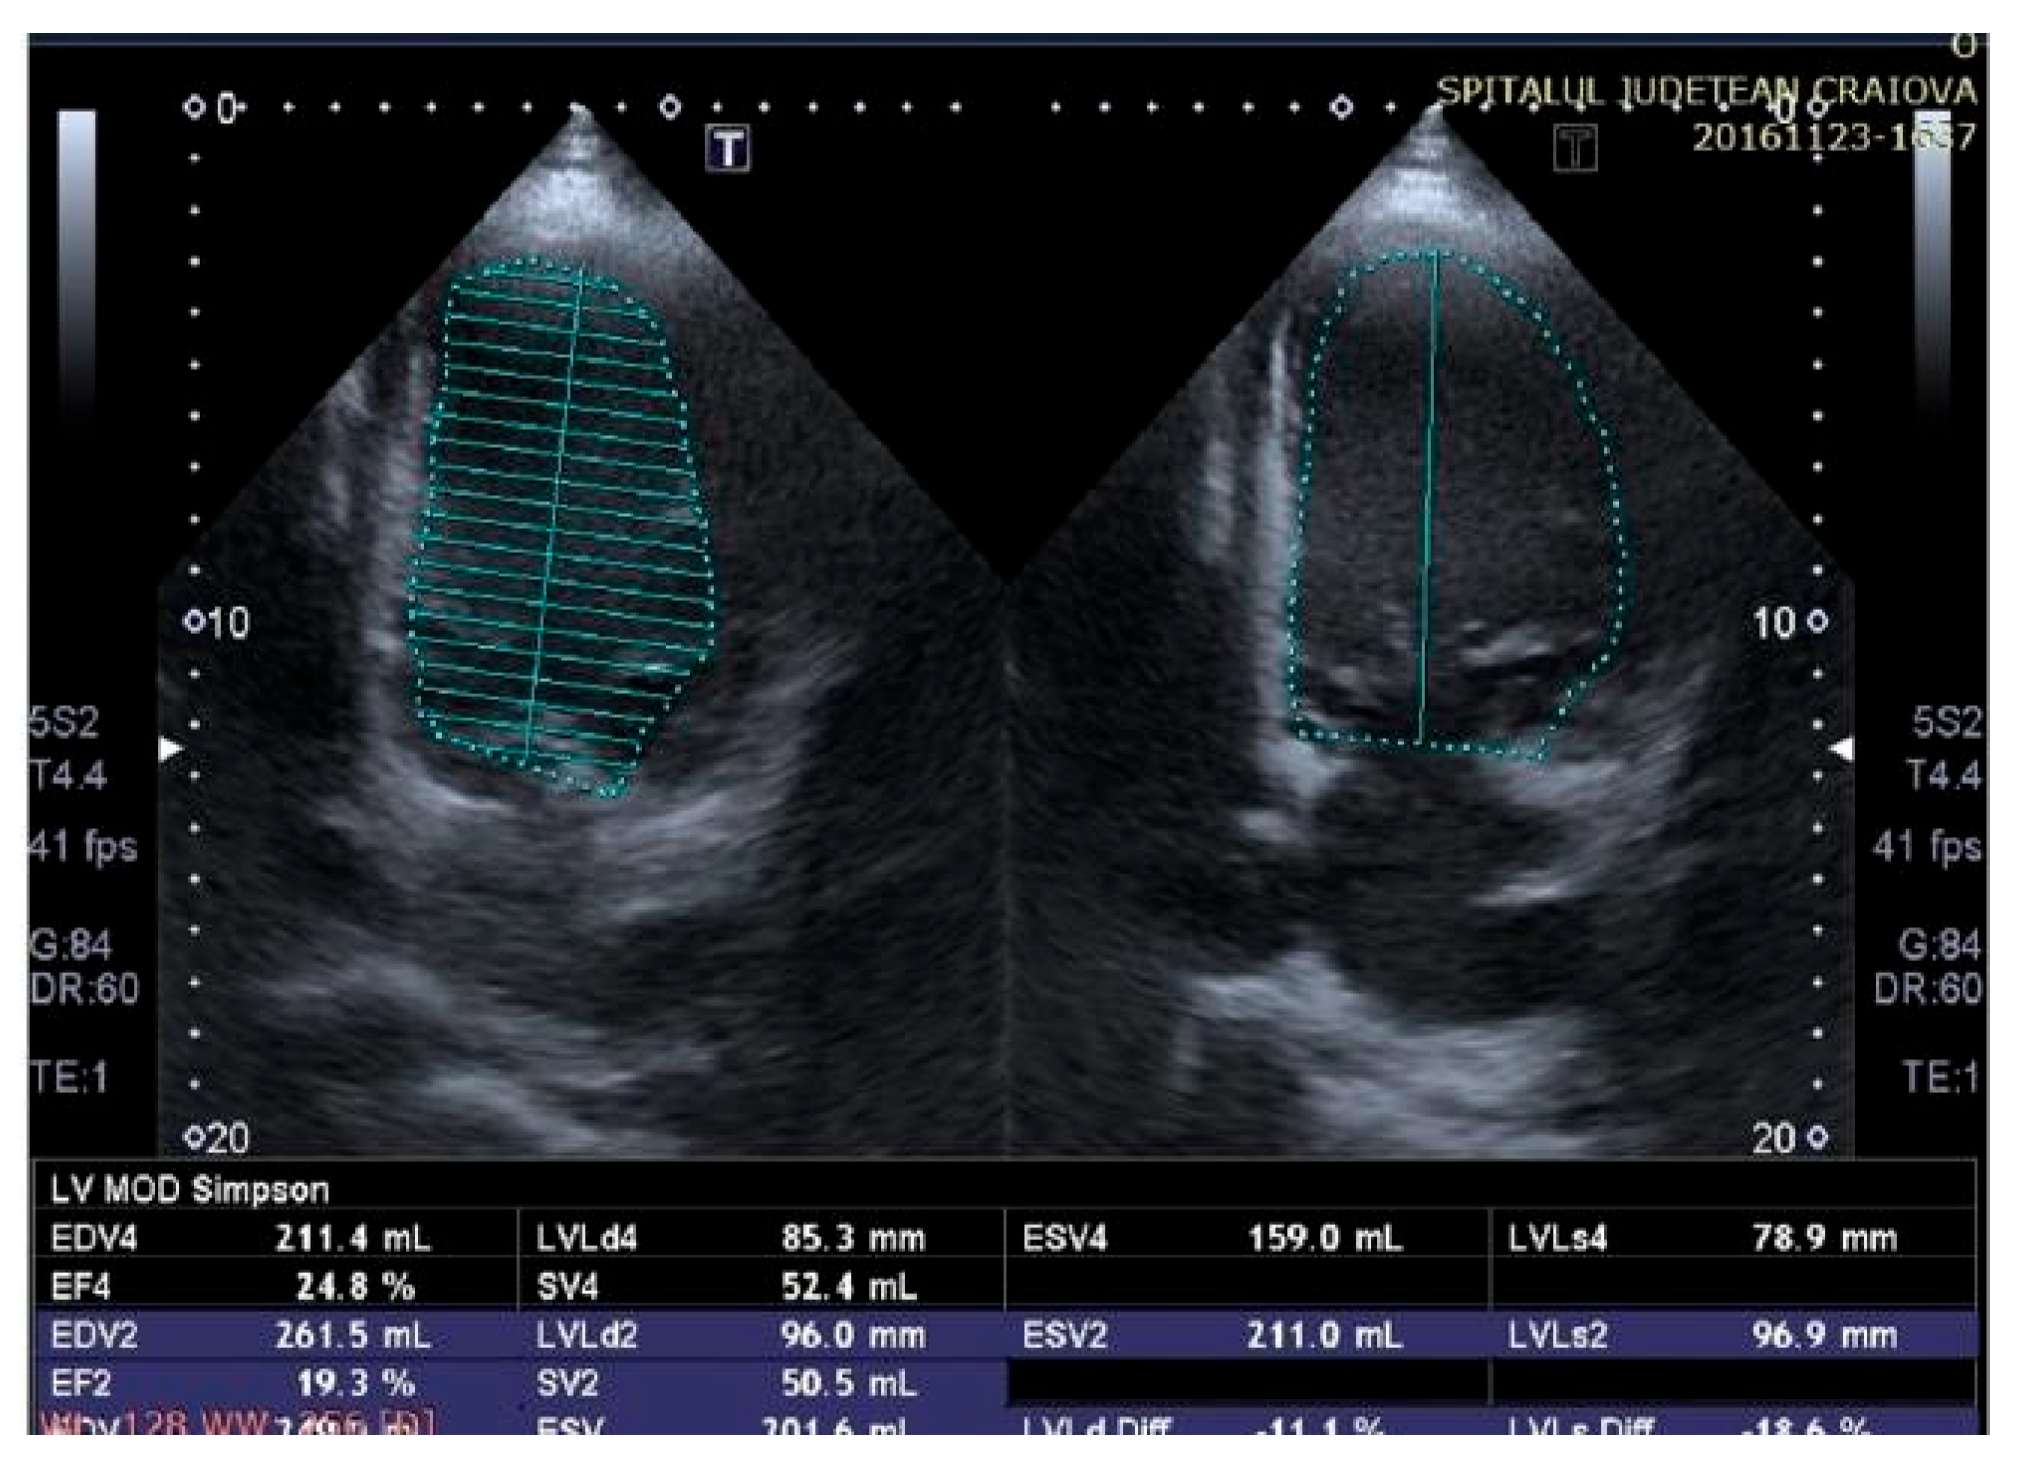

Two-dimensional echocardiography revealed an improvement in left ventricular (LV) function with a low LV ejection fraction (LVEF) of 25% assessed according to the modified Simpson method, after therapy with a cardiac resynchronization device.

Figure 6.